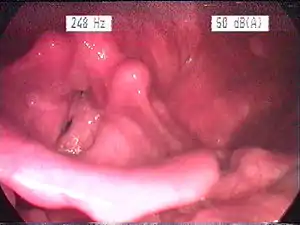

Endoscopic image of an inflamed larynx caused by acid reflux

The larynx itself will often show erythema (reddening) and edema (swelling). This can be seen with laryngoscopy or stroboscopy (method depends on the type of laryngitis).[7]:108 Stroboscopy may be relatively normal or may reveal asymmetry, aperiodicity, and reduced mucosal wave patterns.[22]